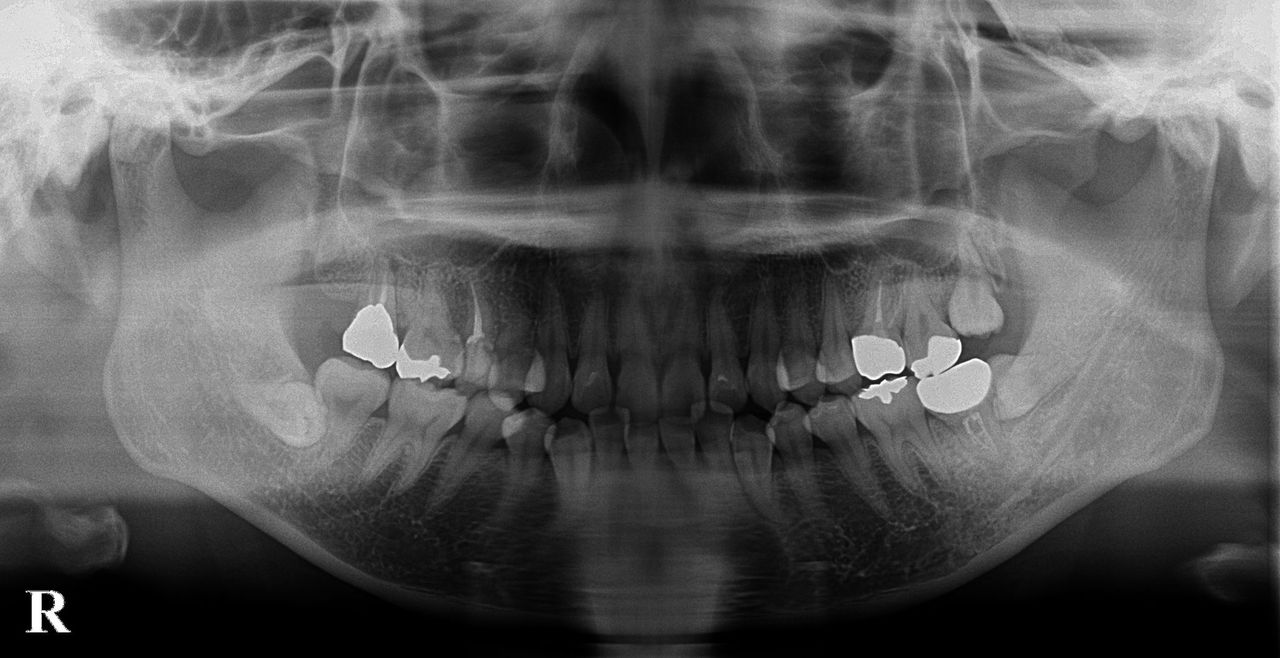

歯牙移植のコツ

今回は歯牙移植についてそのコツをご説明したいと思います。 欠損歯牙補綴手段として最近はインプラントが発達しておりますが、歯牙移植術はインプラントと違って歯根膜まで再生できるため、より生理的状態に近い形で咬合を回復できます […]

歯牙移植について

【歯牙移植ってご存じですか?】 機能していない親知らずなどの歯を歯がないところに移植して機能させる方法です。移植の成功率は約90~70%と言われています。 移植では顎の骨にドナーとなる歯を入れられるだけの穴を空けますが、 […]